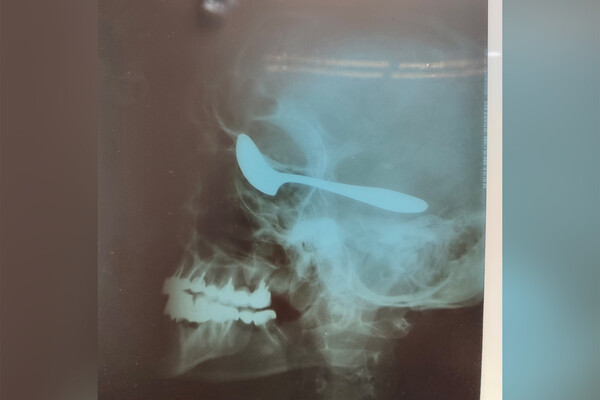

В Чувашии врачи спасли жизнь и зрение мужчине, который в белой горячке вогнал себе ложку в глаз. Об этом сообщает «ЦРБ Алатырского района».

Сообщается, что мужчина поступил в медицинское учреждение с обострением панкреатита. Спустя несколько дней лечения у россиянина произошел алкогольный делирий, называемый также белой горячкой — он набросился на соседа по палате, а затем схватил ложку и воткнул ее себе в глаз.

В связи с произошедшим из республиканской больницы экстренно вызвали нейрохирурга. В это время пациенту провели рентген и компьютерную томографию.